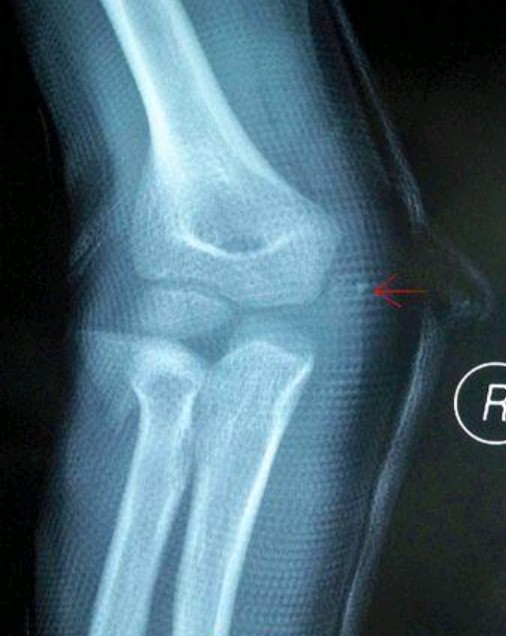

X线表现 肘内侧软组织肿胀;有时可见肱骨内上髁撕脱骨折;肱骨内上髁骨质增生,钙化;有时伴有肱骨小头/桡骨头骨折(外侧撞击引起)MRI表现 T1WI:肱骨内上髁旋前屈肌腱呈中等信号;肱骨内上髁反应性低信号水肿;内侧副韧带撕裂;外侧撞击表现